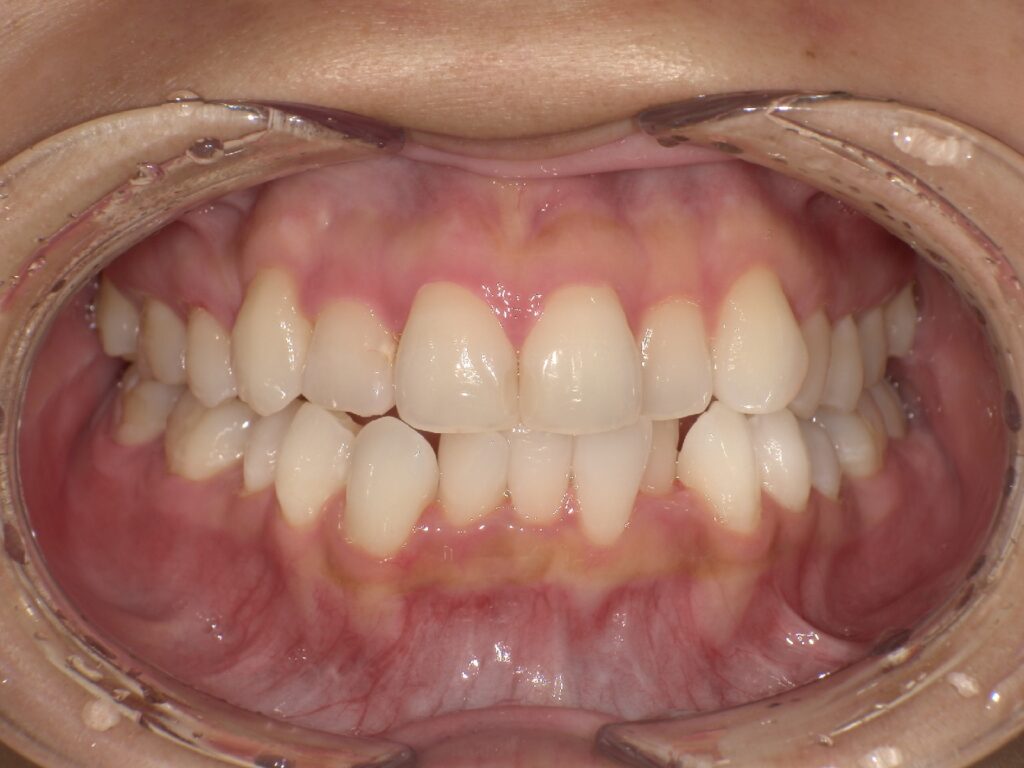

下記のケースでは、奥歯の噛み合わせが悪くなかったことから、患者様の希望もあり、部分矯正で対応いたしました。

上顎の前歯が大きく突出しています

明らかに前歯の突出感が改善し、患者様はこの時点でとても喜ばれていました

矯正治療終了時 部分矯正ということもあり、短期間で矯正治療を終了することができました